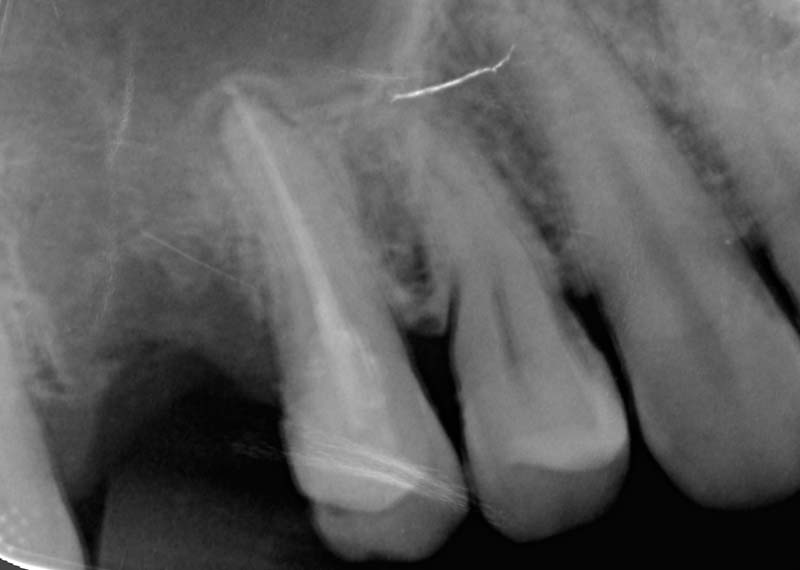

Sometimes the problem goes deeper than what we can see. When bacteria reach the inner nerve of the tooth, it can cause persistent pain or infection.

A root canal treatment (RCT) aims to remove the infection, relieves your pain, and saves your teeth.

For: Compromised pulp (decay or cracked tooth)

We strive for single visit whenever possible